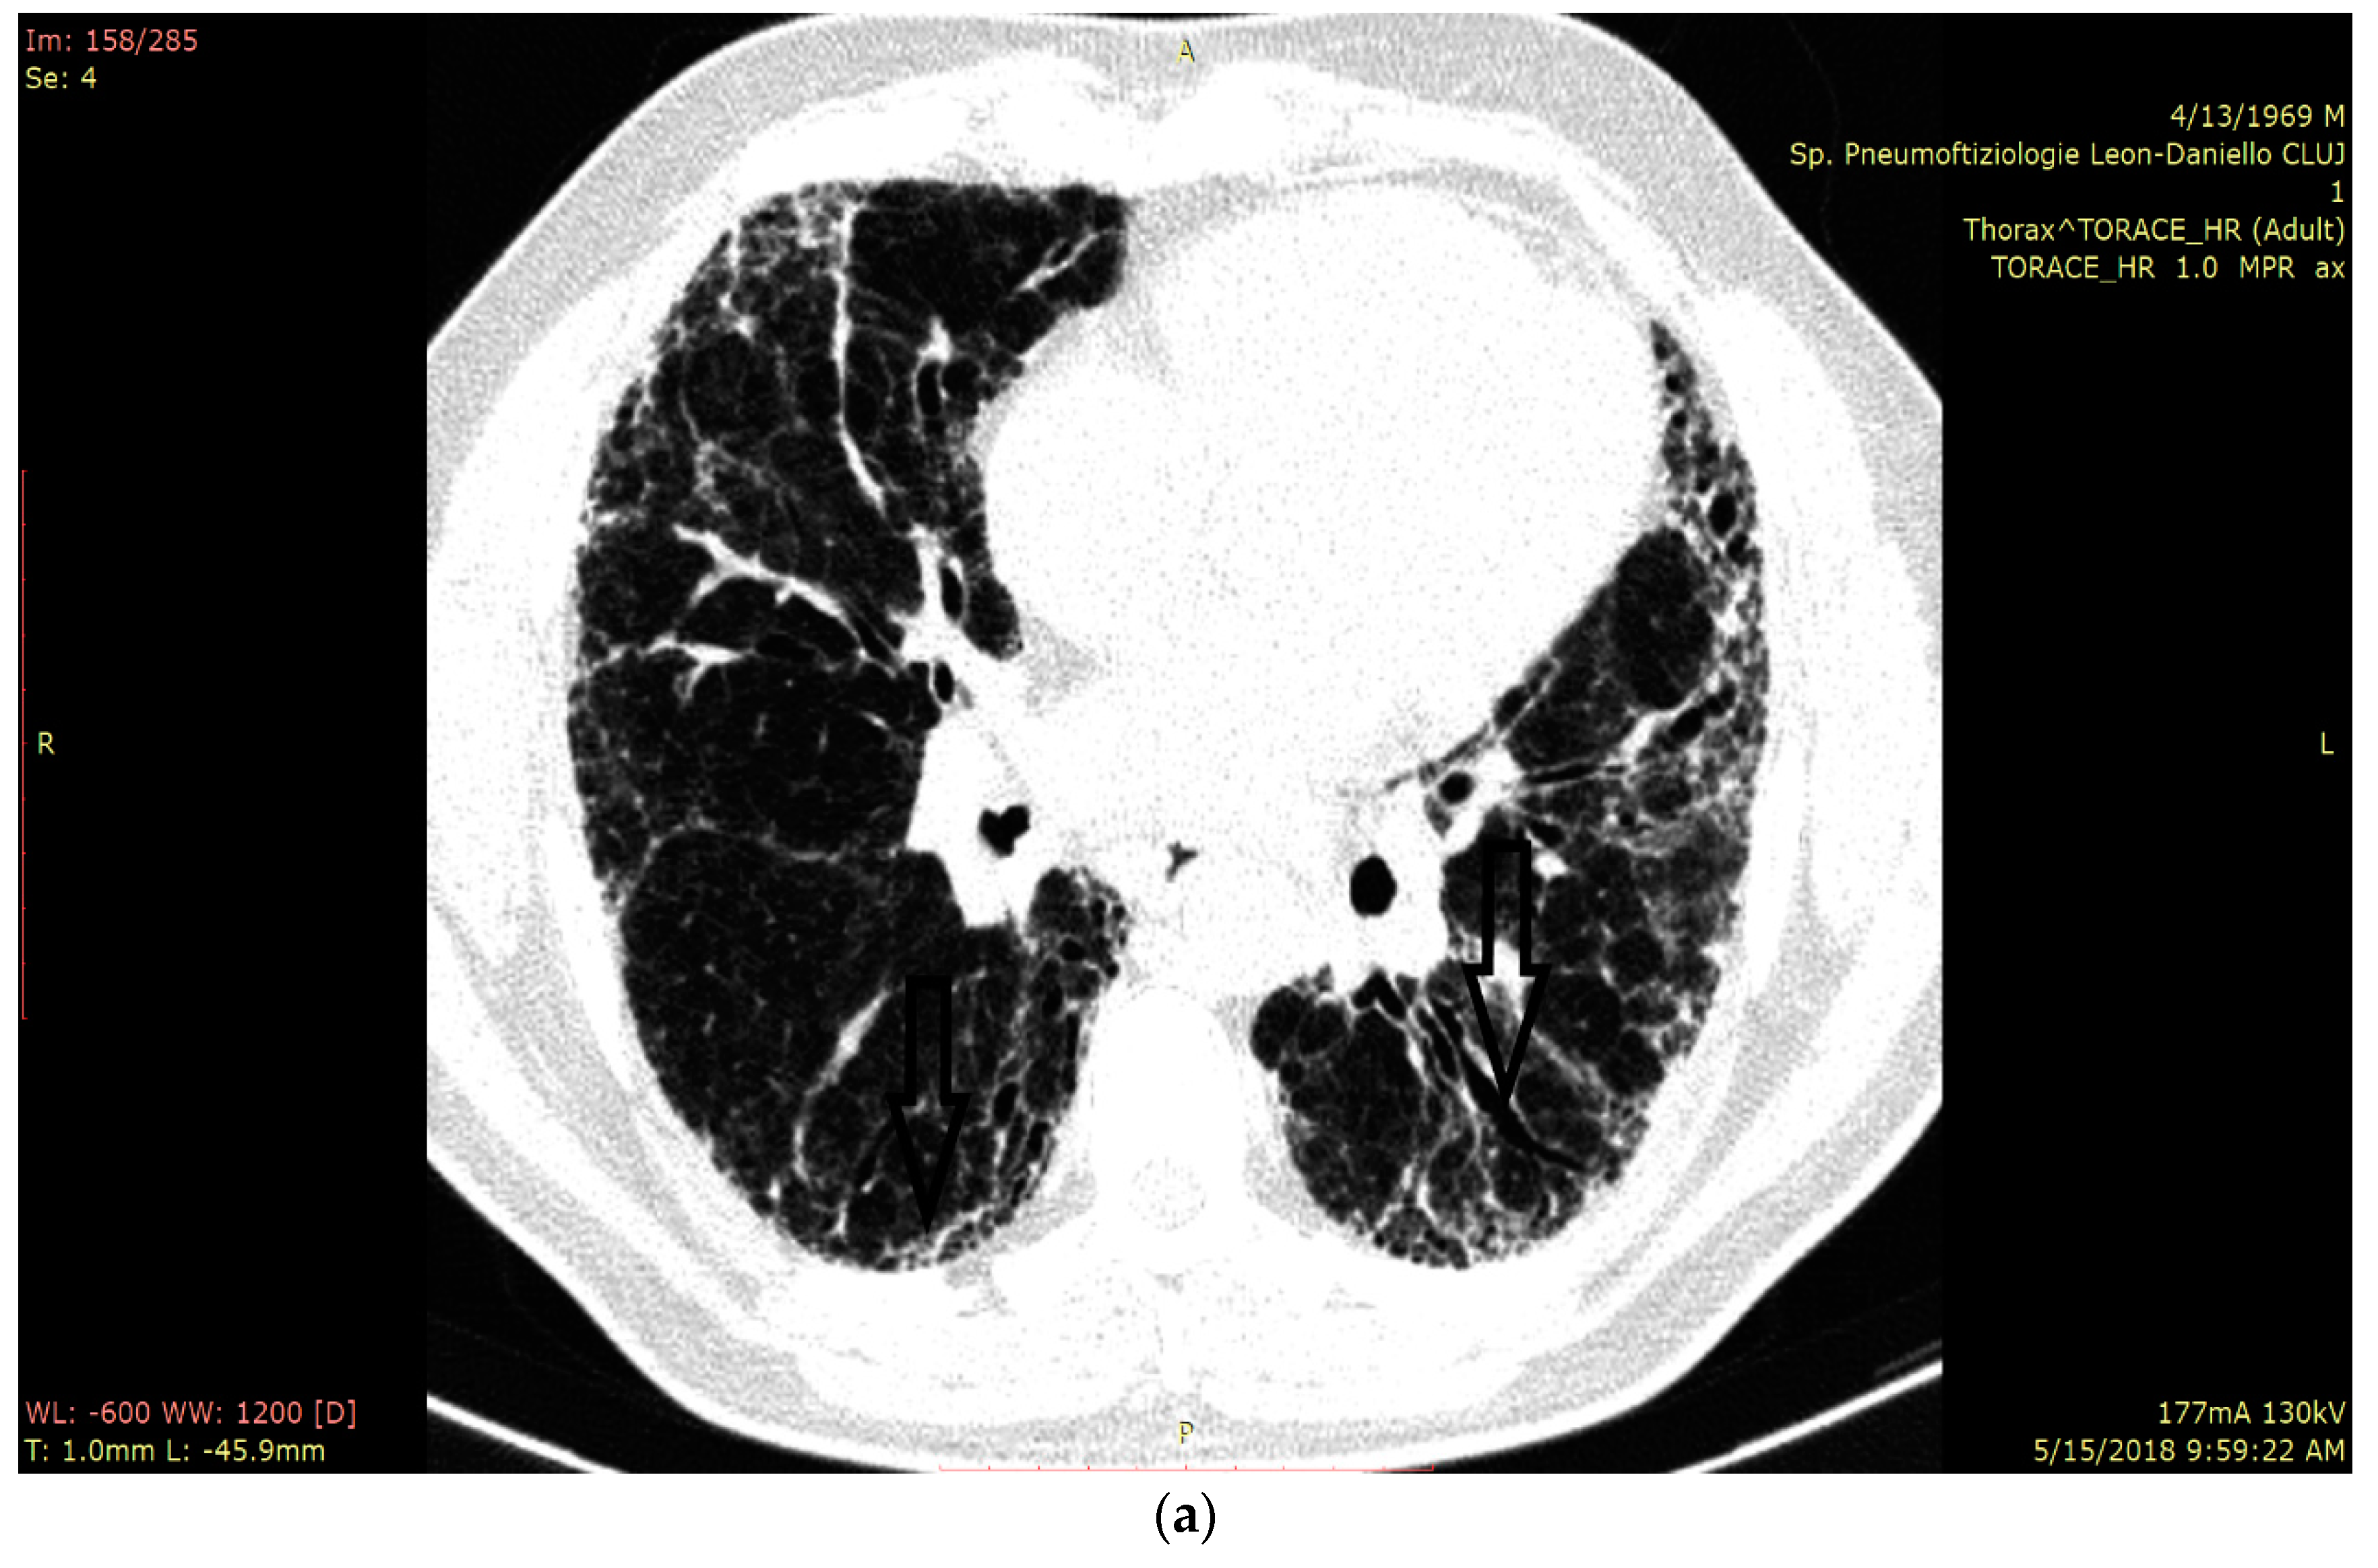

2.4. HRCT Assessment and Disease Quantification

2.5. LUS Assessment and Quantification